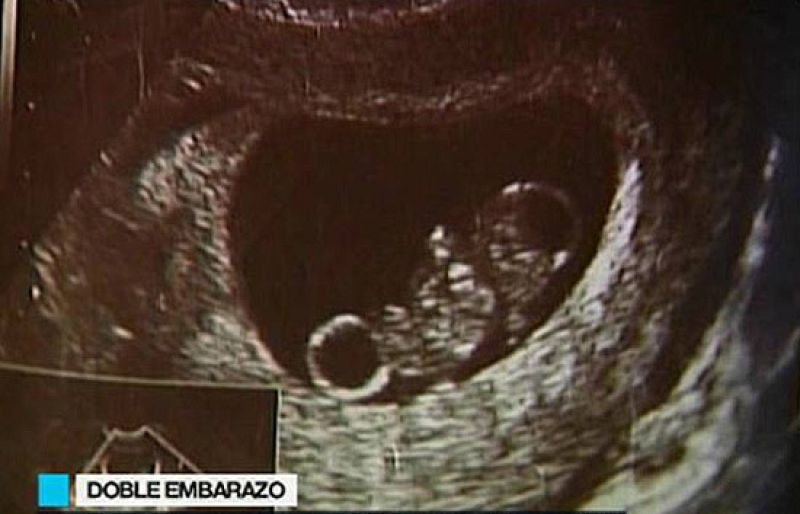

En Estados Unidos una mujer se ha quedado embarazada estando ya embarazada.La pareja fue al ginecológo a una revisión y la ecografía reveló que eran dos bebés y no uno lo que esperaban. Lo más raro de todo es que no son gemelos. Es un fenómeno poco común en humanos y sucede cuando son liberados óvulos procedentes de ciclos menstruales distintos.